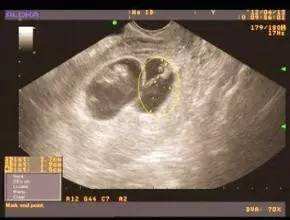

东吴B超监测法 诊断精确 安全无创

在所有测排卵的方法中,准确的就是B超监测法,苏州东吴中西医结合医院利用高分辨的实时超声已广泛应用于卵泡发育及排卵的形态学检查。超声监测的无创、可动态观察卵泡的发育是其优势。也是监测卵泡更直接的方法。在月经周期中,通过仪器可看到卵泡有小到大,由大到无。真真正正的眼见为实,准确无误。